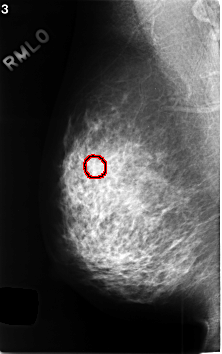

C_0413_1.RIGHT_MLO

FILE: C_0413_1.RIGHT_MLO.OVERLAY

TOTAL_ABNORMALITIES 1

ABNORMALITY 1

LESION_TYPE CALCIFICATION TYPE AMORPHOUS DISTRIBUTION CLUSTERED

ASSESSMENT 4

SUBTLETY 4

PATHOLOGY BENIGN

TOTAL_OUTLINES 1

BOUNDARY